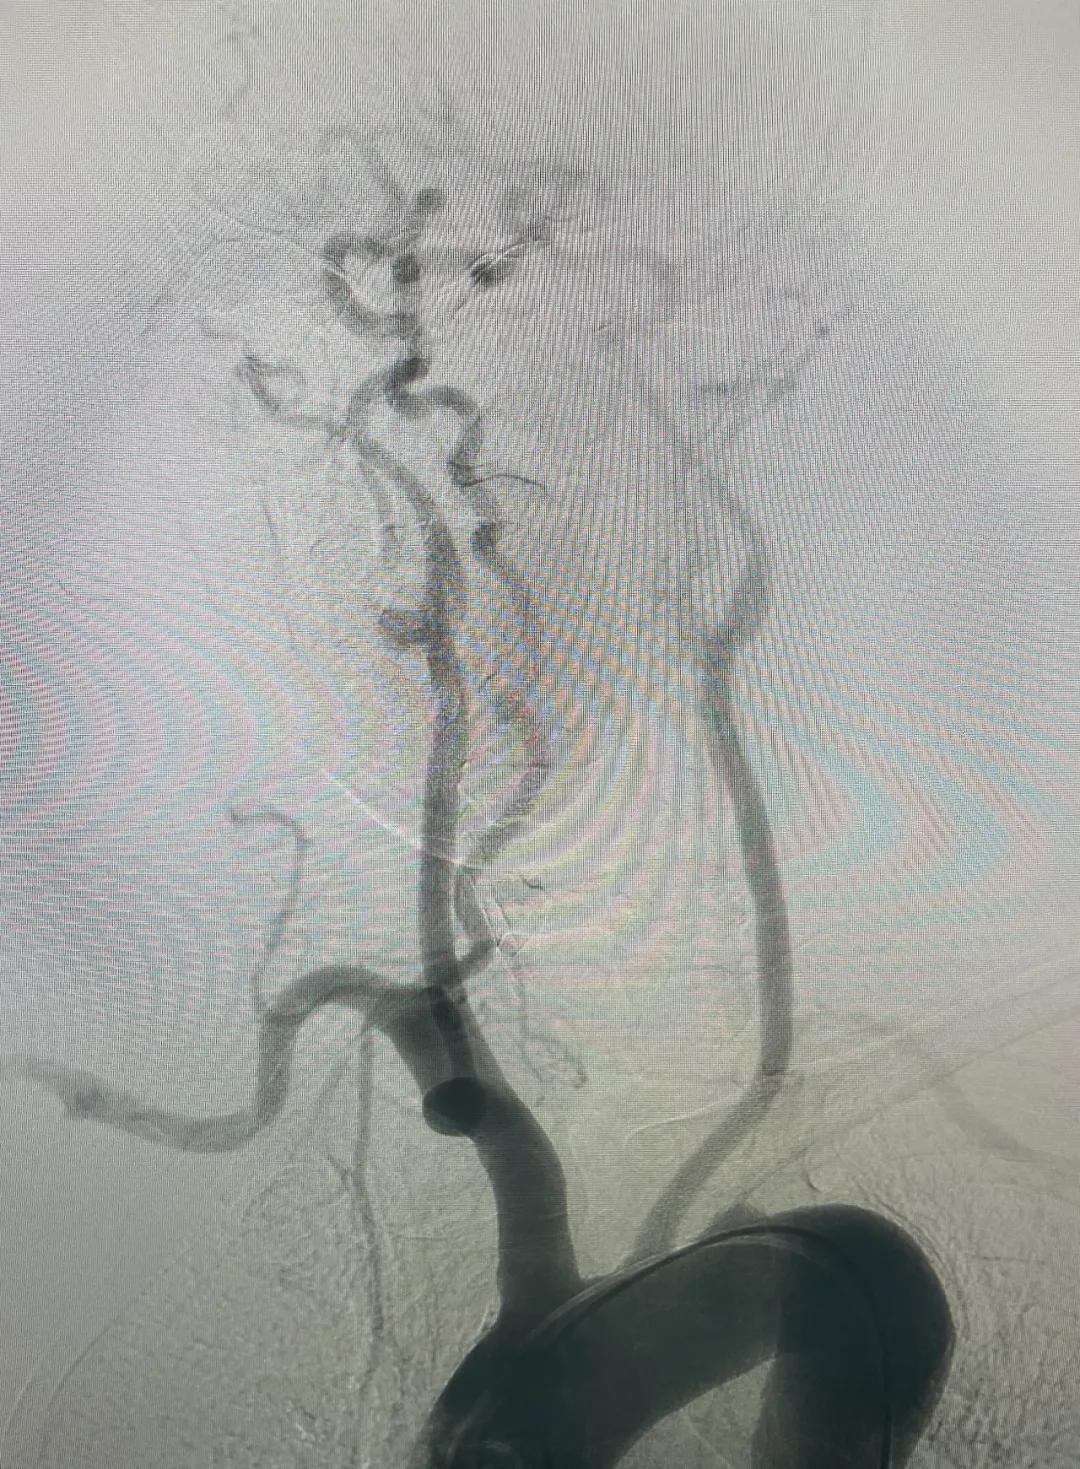

【介入新时代】乌兰察布市中医蒙医综合医院首例全脑血管造影术成功,开启脑血管诊疗新征程

2025年2月8日上午,乌兰察布市中医蒙医综合医院迎来了一个振奋人心的时刻:在多方紧密配合下,首例全脑血管造影术成功实施。手术顺利完成,患者术后情况稳定,这不仅是医院发展的重要里程碑,更为乌兰察布及周边地区百姓的脑血管健康带来了福音。

全脑血管造影术是脑血管疾病诊断的“金标准”,能精准显示脑血管形态和病变,为后续治疗提供关键信息。这次手术成功,展现了医院神经内科团队的专业实力,也体现了多学科协作的高效。

全脑血管造影术:精准锁定脑血管病变,为后续治疗筑牢根基。